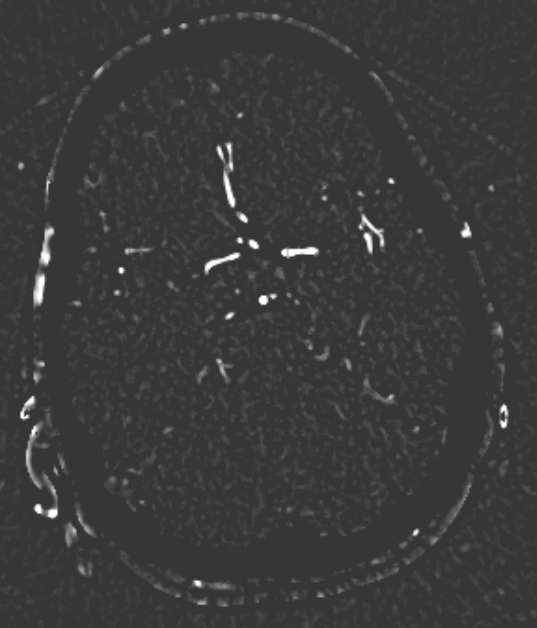

Refer to caption

(e) Frangid

(f) Mask(e)

The pipeline we propose receives a CTA image as input, an example of which is shown in Fig. 2(a). Alongside the CTA data, a brain atlas (shown already registered to an example in Fig. 2(c), a mean brain over a patient populations) (Kemmling et al., 2012) together with the corresponding vessel atlas (Forkert et al., 2012) (accordingly transformed, shown in Fig. 2(d)) is given. The latter atlas is a volume representing the existence of voxels belonging to a vessel by means of a probability value, whereby it emphasizes on the arterial branches close to the Circle of Willis. In a first step, all bone structures are removed, as indicated in Fig. 2(a), using a method by Chen et al. (2020) which segments those bone structures in CTA scans. An example is shown in Fig. 2(b) which is the bone segmentation of the slice shown in Fig. 2(a). The CTA volume is not only forwarded to the bone removal but also used to register the brain atlas onto in Fig. 2(b). The non-rigid (elastic) registration is based on Chefd’Hotel et al. (2002)’s method specifically designed to register multi-modal volumes. The resulting deformation field is used to transform the vessel atlas (Forkert et al., 2012) in step Fig. 2(c) into the CTA coordinate system. Tubular structures of the bone-free CTA scan, resulting from Fig. 2(a), are enhanced using the Frangi filter (Frangi et al., 1998) (two scales, σ1=1.00subscript𝜎11.00\sigma_{1}=1.00, σu=1.50subscript𝜎𝑢1.50\sigma_{u}=1.50) exemplarily shown in Fig. 2(e). The filter response is masked in Fig. 2(e) with the vessel atlas, which is binarized with a relative threshold of t1=0.5%subscript𝑡1percent0.5t_{1}=0.5\% (of the maximum value) followed by dilation (with a kernel size in z,y and x of 11, 7 and 7, respectively). Fig. 2(f) shows the result of the vessel masked Frangi response, which is thresholded with t2=4subscript𝑡24t_{2}=4. Values below that threshold are suppressed to zero, values above are kept with the original values. With this step, noise is being reduced which stabilizes the subsequent steps, like the slice-wise circle based Hough transformation in step Fig. 2(f)(canny threshold = 10, accumulator threshold = 1, min distance = 5, min radius = 0, max radius = 5 and accumulator threshold = 1). The goal of the Hough transformation is to identify circle-shaped structures in the given slices, however, as shown in Fig. 2(g) many centerpoints of the detected circles do not match with the preliminary vessel tree segmentation. Hence in the next step, the mask used for the Hough transform is reused again, to mask out in step Fig. 2(g) all centerpoints which do not align with the segmentation. The example shown in Fig. 2(g) originally has 6747 centerpoints in total, reduced to 1375 by the masking, the result of which is shown in Fig. 2(h). The remaining points are used as seed points for region growing in Fig. 2(h). The region growing segments all voxels connected to the seed points, whose intensity differs no more than ±5%plus-or-minuspercent5\pm 5\% from the average intensity of the seed point voxel values. The result is a preliminary segmentation which only includes vessel segments represented in the original vessel atlas. As will be described below, this mask is used for labeling. The result is shown in Fig. 2(i). In order to segment all vessels, especially more distant vessel structures, the segmentation mask of step Fig. 2(h) is transformed into seed points which are used for the final region growing in Fig. 2(h) segmenting every connected voxel with a value in the range of 130 HU to 1500 HU. Its result is the final segmentation, shown in Fig. 2(j). The whole pipeline has been implemented in MeVisLab 3.4, MeVis Medical Solutions AG, Bremen.